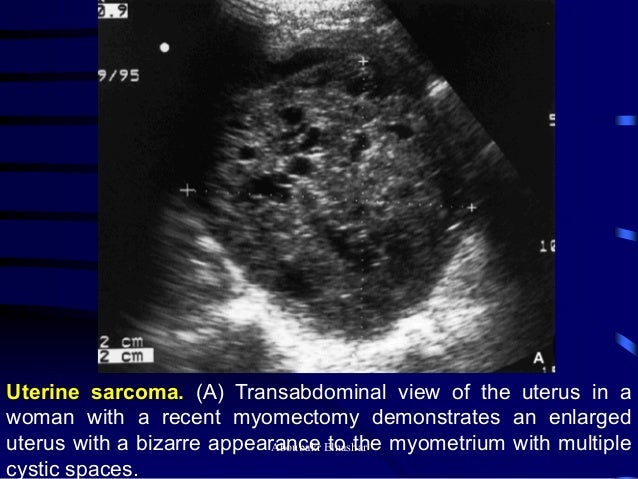

Find out all about Echotexture 📙 meaning, pronunciation, synonyms, antonyms, origin, difficulty, usage index and more Only at Word Panda dictionaryHeterogeneous and record their diagnostic confidence level using a 5point Likert scale LIVER ECHOTEXTURE METHODS Six weeks later, Reviewers participated in a liver echotexture tutorial which demonstrated use of the spleen as an internal reference, and after approximately 4 additional weeks, the same 64 scans were newly rerandomized and rereviewed LIVER ECHOTEXTUREThe uterus is borderline enlarged and shows heterogeneous echotexture, which is nonspecific Abnormal tissues such as cystic nodules, adenomas and cancerous tumors appear as heterogeneous structures in thyroid ultrasound imagery Cancer of the Uterus Endometrial Cancer What is adenomyosis or bulky uterus?

Initially, it invades the myometrium of the uterus, then the endocervix After transerosal spread, direct invasion of bladder and bowel can occur, as well as metastasis to the lungs Endometrial cancer treatment usually involves surgical removal of the uterus, ovaries and fallopian tubes In some cases, it will be necessary to undergo radiation treatment, chemotherapy'Heterogenous uterus' is a description used to describe the appearance of the uterus after an ultrasound exam is done All that this means is that the ultrasound appearance of the uterus is not totally uniform The two most common causes of heterogenous uterus are uterine fibroids, which are benign muscular growths in the uterine wall, and adenomyosis, which is a proliferation of theHeterogeneous uterus fibroid Uterine fibroid s, also known as uterine leiomyomas or fibroid s, are benign smooth muscle tumors of the uterusMost women have no symptoms while others may have painful or heavy periods

what does this possibly mean The uterus is borderline enlarged and shows heterogeneous echotexture, which is nonspecific A uterine fibroid in the anterior body is possible Heterogeneous medical condition or heterogeneous disease in medicine are those medical conditions which have several etiologies, like hepatitis or diabetes The word is used as an opposition to homogeneous, meaning that given a group of patients, the disease isIn some cases, the sole clue to the presence of leiomyoma on US is an irregularly enlarged uterus with distortion or obscuration of the endometrial stripe 6 When seen as discrete lesions, leiomyomas may appear hyperechoic or hypoechoic, homogeneous, or heterogeneous Regardless of their echogenicity or echotexture, shadowing and attenuation